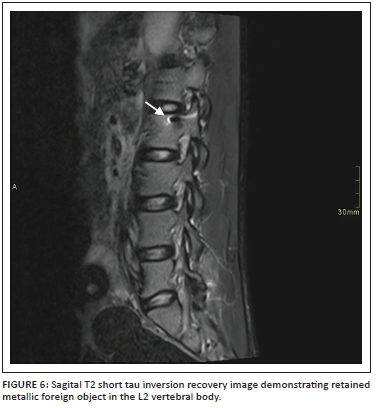

Spinal radiography was performed in 32.1% (n = 18) of the patients, while computed tomography (CT) was performed in 41.1% (n = 23). Metallic foreign material was noted in two of our study patients on MRI, of which one patient did not receive X-rays or a CT scan prior to the MRI.

Migration of ferromagnetic components remains a concern with MRI.18 Prior to MRI, spinal X-rays and CT scans are helpful to evaluate the extent of bone injury, the penetrating wound trajectory, the presence of foreign material (especially metallic), bone fragments or air.19 Metallic foreign material was noted in two of our patients on MRI, of which one patient did not receive X-rays or a CT scan prior to the MRI. Although spinal radiography was performed in only 32.1% (n = 18) and CT was performed in only 41.1% (n = 23) of the patients, we suggest that all patients receive X-rays or CT prior to MRI to rule out the presence of metallic foreign material.

In our study, the majority (94.6%) of the patients had T2-weighted sagittal imaging, while 91.1% of cases had sagittal T2 STIR included. Even though T1- and T2-axial imaging does not serve prognostication purposes,11 it does aid in deciding whether haematoma is intra- or extra-axial. In our experience, cord laceration was best depicted on T2 STIR sagittal images (Figure 3), while fluid collections were best seen on T2 STIR and T2 sagittal images (Figure 4). Gradient recalled echo images were the best at depicting cord haemorrhage (Figure 5) although without spinal X-rays and CT, there is difficulty in differentiating intra-spinal air and foreign fragments (Figure 6) from haemorrhage.